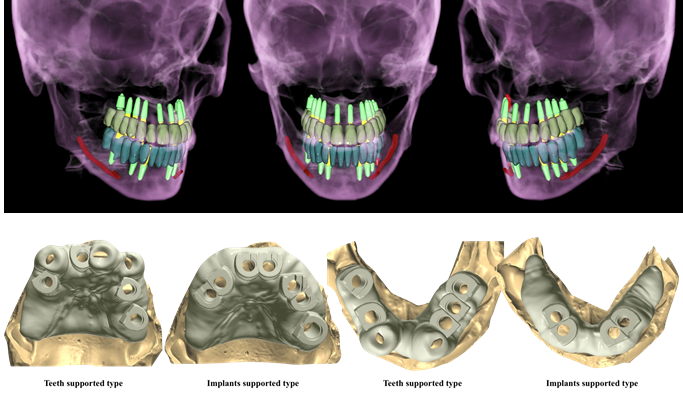

Effective R2STUDIO in complex tooth positioning

- Courtesy of Dr. Jong Cheol Kim, Korea

Dr. Jong Cheol Kim, edentulous, digital full-mouth prosthetics, digital guided surgery, guided surgery,R2 Studio, R2GATE Digital Oral Design, R2GATE DOD,flapless, AnyRidge, R2GATE, R2GATE full surgical Kit

AnyRidge implant system, R2GATE Guide, R2GATE surgical kit, R2GATE DOD, R2 Studio